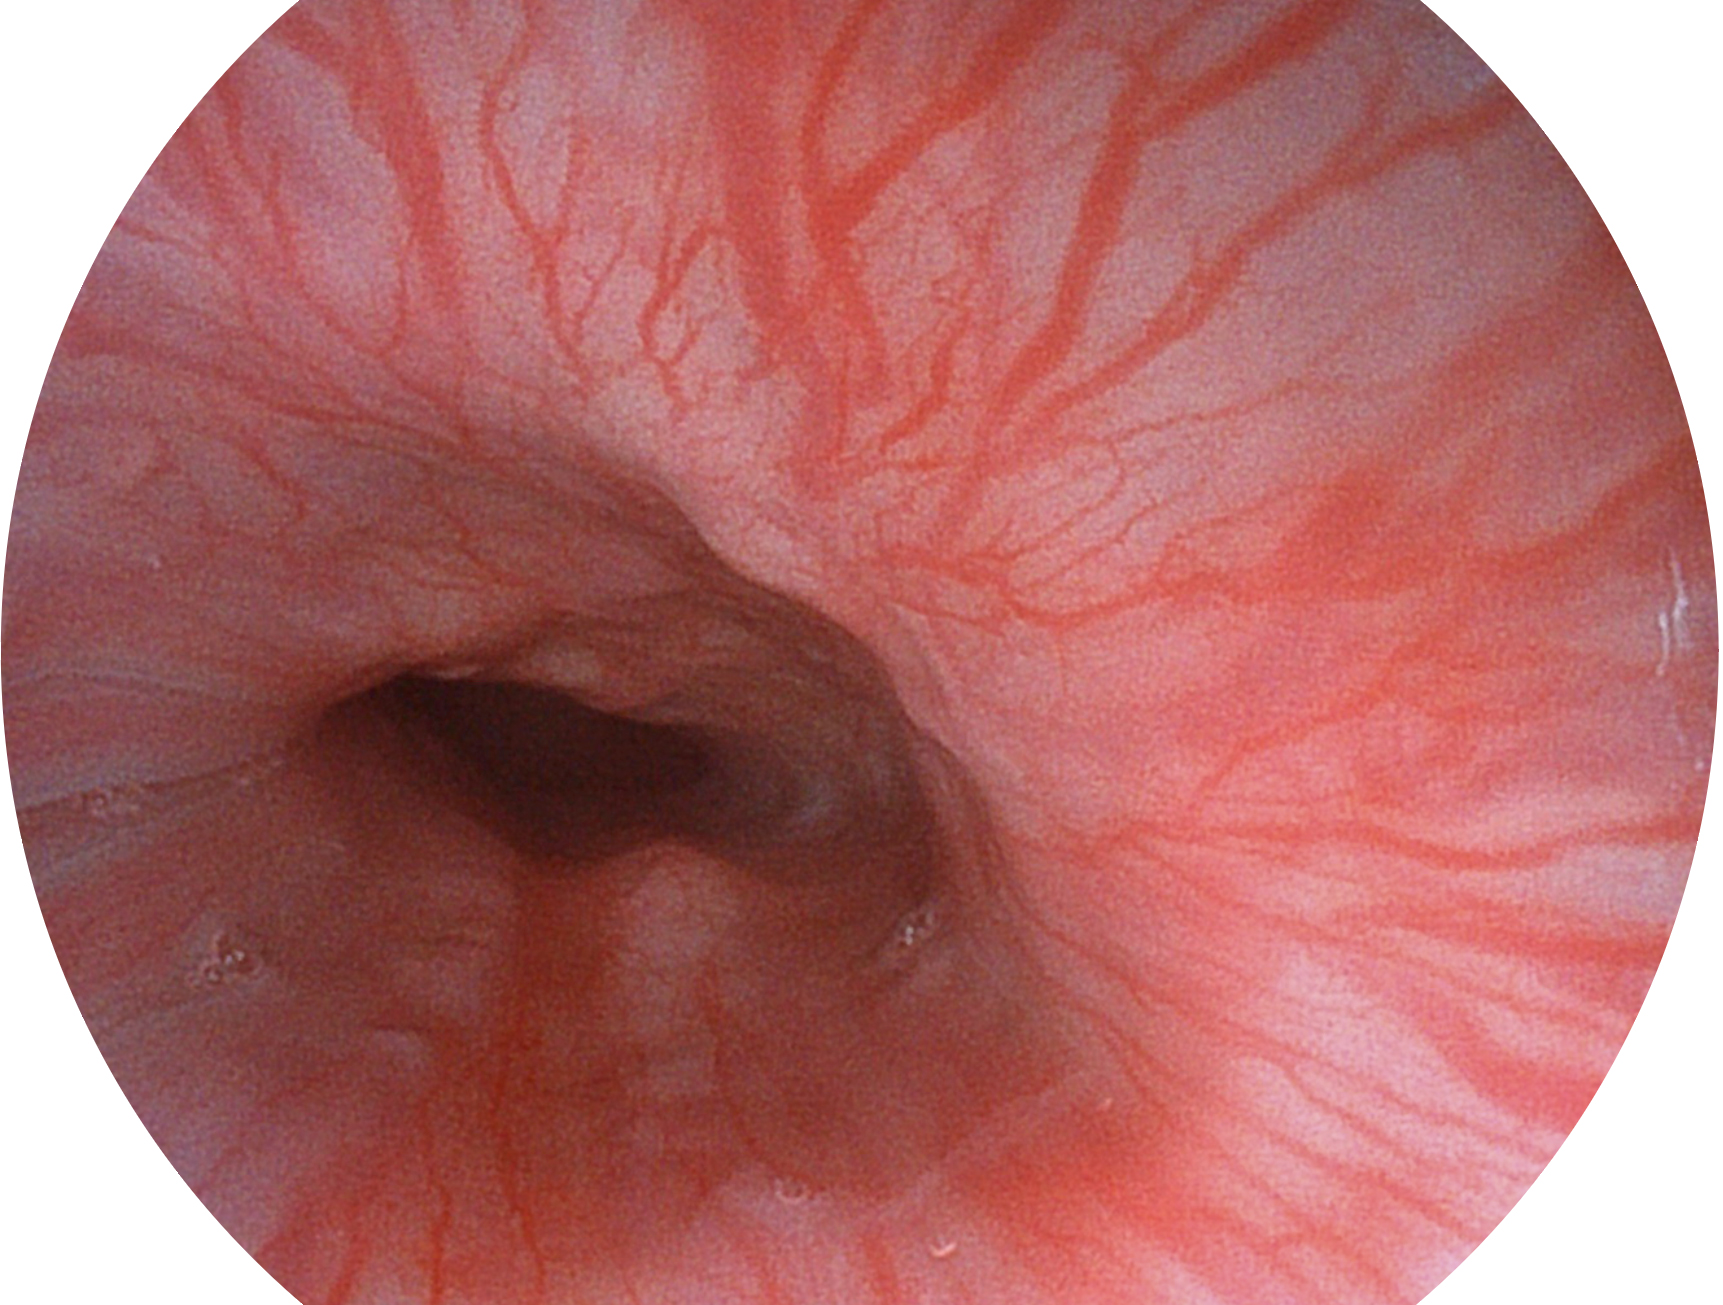

開立新開發(fā)的內(nèi)鏡染色技術(shù),主要是基于多波長LED 光源的開發(fā),VLS-55Q 四波長LED 光源是由四個不同顏色的LED光按照相應(yīng)照明模式所規(guī)定的特定發(fā)光比例進行合束后形成,合束后形成的照明光的光譜由紅光、綠光、藍光及藍紫光這四個不同的波段范圍構(gòu)成。具有更高光譜自由度,通過光譜比例的控制,實現(xiàn)了聚譜成像技術(shù),英文全稱為“Spectral Focused Imaging, SFI”,縮寫為“SFI”和光電復(fù)合染色成像技術(shù),英文全稱為“Versatile Intelligent Staining Technology, VIST”,縮寫為“VIST”。